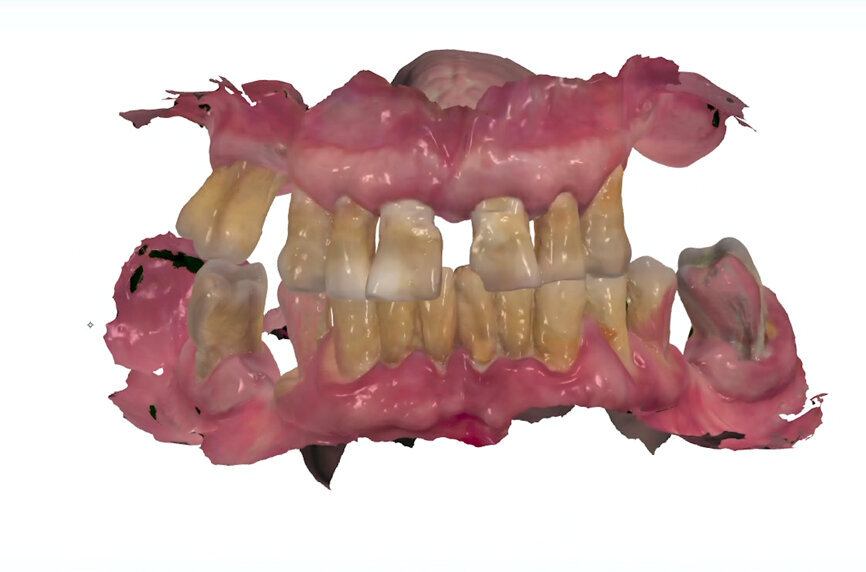

Before starting the surgery, an initial study model scan was obtained with the intra-oral scanner and sent to the laboratory as the patient’s original file (File 1). This file contained all of the information concerning the patient’s preoperative situation, including teeth, aesthetics, vertical dimension of occlusion and occlusion (Fig. 3).

To obtain the final intra-oral surface scan, original Straumann SRA scan bodies were connected to the SRAs under visual control (Fig. 10). A new intra-oral scan was taken to record the patient’s current oral situation, showing the scan bodies and the preserved strategic teeth. This file (File 2) was also sent to the laboratory (Figs. 11 & 12). When the laboratory confirmed receipt of both files, the preserved teeth were extracted and healing caps placed on the abutments, completing the surgery.

On receipt of the scan body file (File 2), the laboratory imported it into 3Shape’s Dental System and created a virtual model, matching the virtual SRA scan bodies from Straumann’s original library with the intra-oral SRA scan bodies (Figs. 13 & 14). A working file was created for designing the temporary prosthetic emergence profile for the SRA.

To perform the design of the temporary full-arch prosthesis and maintain (or modify) the vertical dimension of occlusion and occlusion, the patient’s pre-preparation study model scan file (File 1) was imported as a pre-preparation scan (blue) and merged with the implant file scan (File 2), using the preserved teeth present on both scans. The software allowed us to mark the same points on the preserved teeth on both files, the study model scan and the implant scan (both contained the preserved teeth). Thus, the laboratory was able to work on a single file containing both Files 1 and 2, merged by means of the preserved teeth. Designing the temporary prosthesis is an easy task using the image of the patient’s own teeth as a mock to be copied (Fig. 15). Any design modification can easily be done (Figs. 16 & 17).